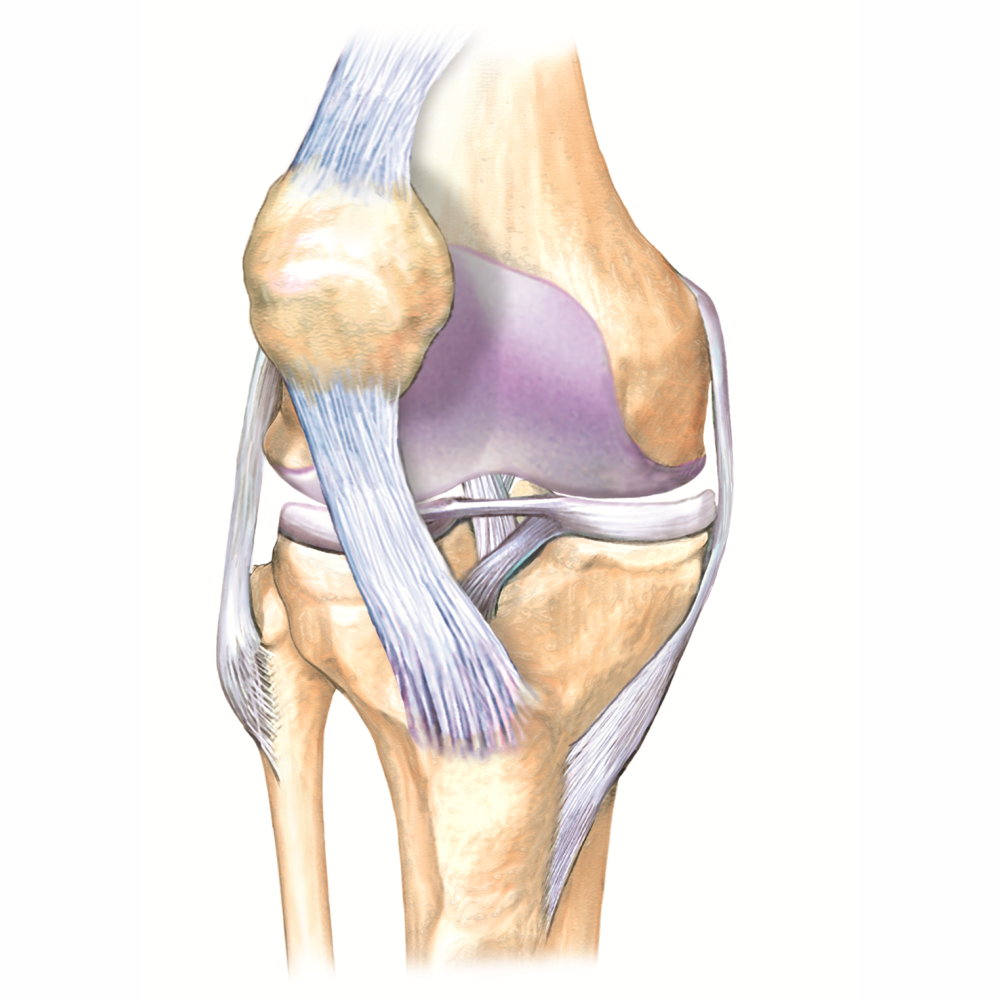

Анатомические изображения менисков и коленного сустава

Раздел: Иллюстрированные советы